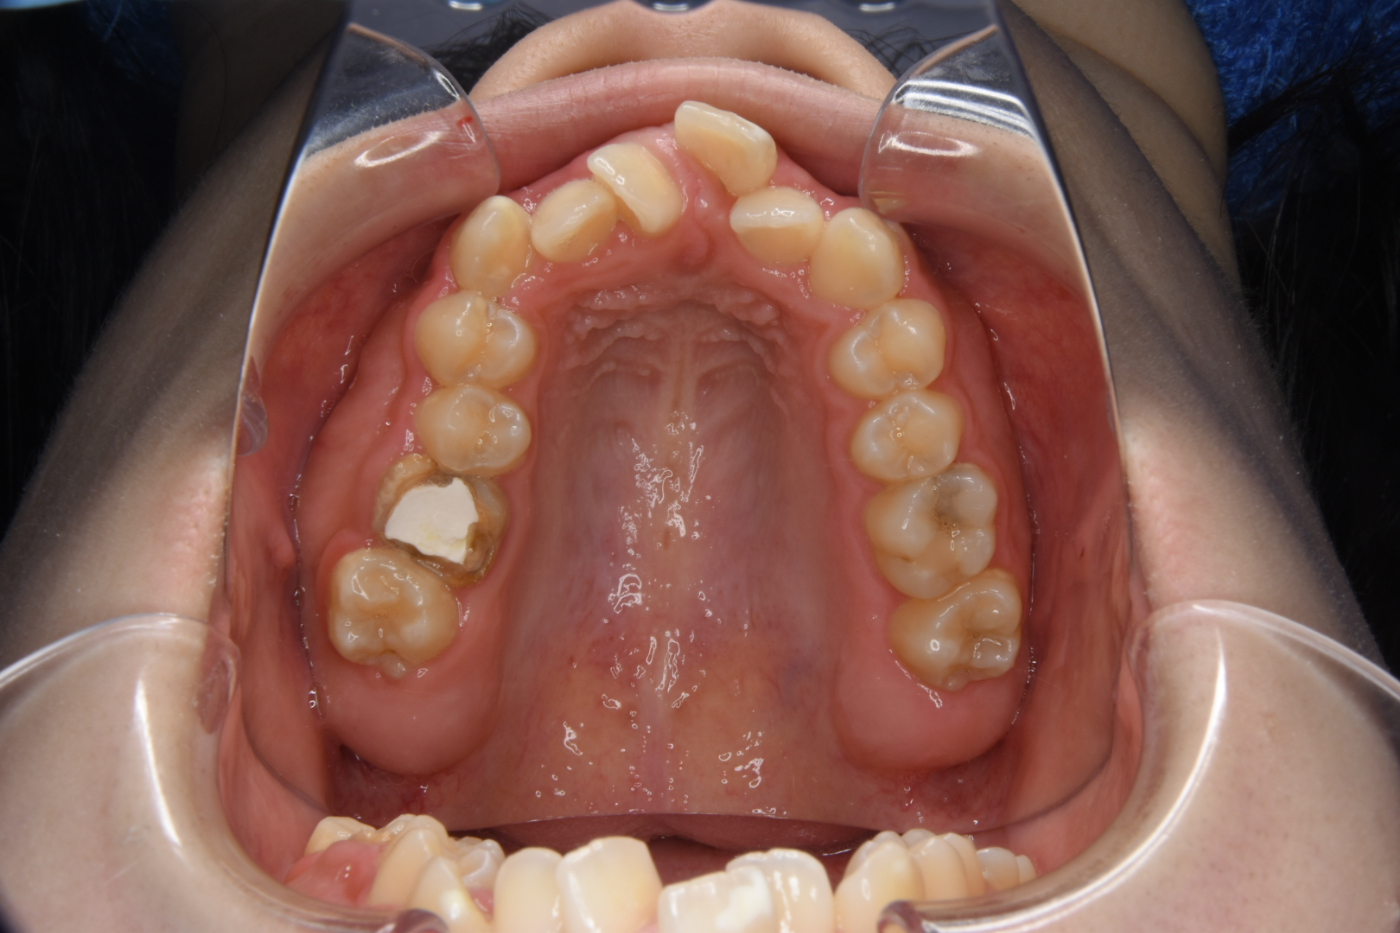

叢生(そうせい)・乱杭歯(らんくいば)

いわゆる「がたがた」「でこぼこ」、または「八重歯」といわれる状態です。

アゴの骨と歯のサイズのバランスが悪かったり、乳歯が通常より早く抜けてしまうことで歯が不規則に移動したりすることで、歯が重なり合って生えてしまっています。大人になってからでも、でこぼこを綺麗に矯正することが可能です。

顎の大きさが小さいために、歯が並ぶスペースが不足すると歯並びがガタガタする原因となります。また、顎の大きさに比べて歯が大きすぎることが原因で叢生になる場合もあります。そのほか、虫歯や怪我などで乳歯を早く失ってしまったことで、空いたスペースに歯が移動して永久歯が生えるスペースが失われることもあります。

Before

Before

Before